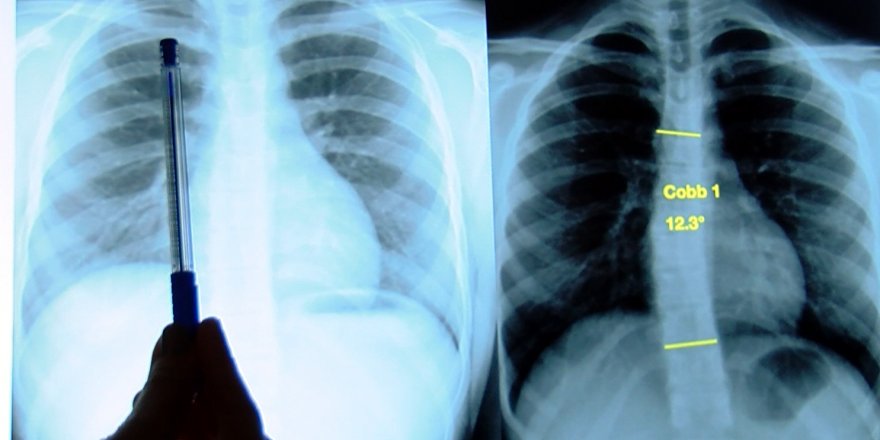

ERGENLİĞİN KÖTÜ SÜRPRİZİ SKOLYOZDA EZBER BOZAN ARAŞTIRMA